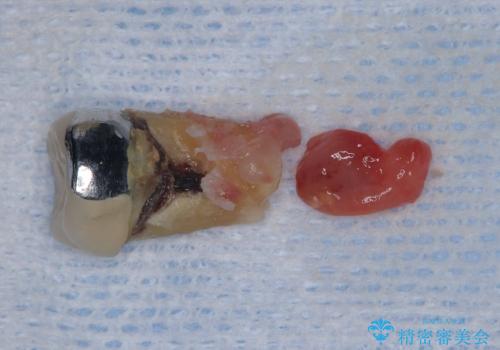

- 過去にヘミセクションが行われていたと思われる左下7番は、大きな歯根嚢胞および根尖病変が認められ、さらに骨縁下カリエスを伴っており、歯肉には瘻孔が形成されている状態でした。

保存は困難と判断し、左下7番は抜歯即時インプラントによる治療を行いました。